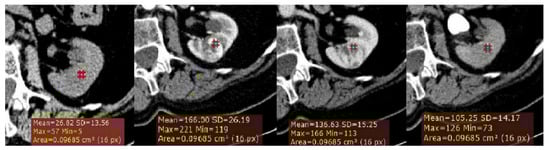

2.3. CT Image Analysis